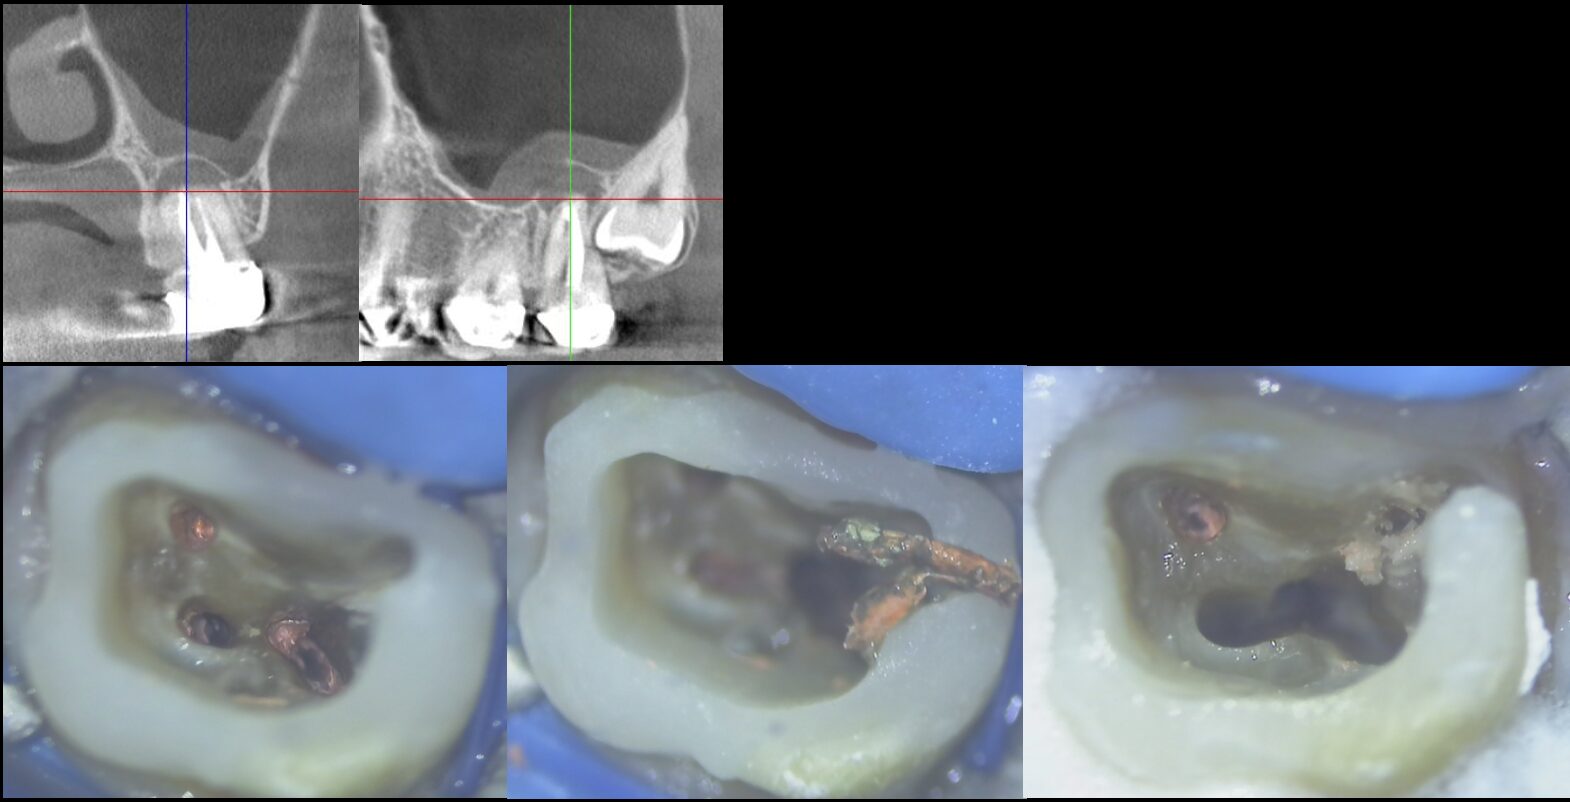

上顎洞へ交通する根尖性歯周炎(歯髄壊死)の再治療

- 主訴

- 噛むと痛い。走ったり、下を向くと、歯の奥が響く

- 治療内容

- 左上第二大臼歯

かかりつけ医より、ご紹介をいただき、根管治療の引き継ぎとなりました。

歯が猛烈に痛くなり、かかりつけ医で診察を受けたところ、歯髄壊死と根尖性歯周炎と診断され、応急処置として大まかな炎症を取り除いてもらいました。

①左上の一番奥の歯で器具が届きにくいこと。 また、治療がテクニックセンシティブな歯であること

②上顎洞と病変が交通していること

などを考慮されて、かかりつけ医の先生より、根管治療専門医での治療を勧められ、ご紹介来院されました。

CT所見では、病変が上顎洞底を突き抜け、上顎洞内への道を作っている状態でした。

治療後3ヶ月後のCT検査では、病変の縮小傾向を認め、上顎洞と病変の交通も遮断され改善されていました。

治癒を確認し、最終補綴は、ご紹介頂いたかかりつけ医で行っていただきました。

- 治療期間

- 2回

- 治療のリスク

- 上顎洞と病変が交通しているため、根管内を洗浄する薬液や、根管充填材などの異物が、上顎洞に入り込まないように、細心の注意を払う必要があった。

BEFORE

AFTER